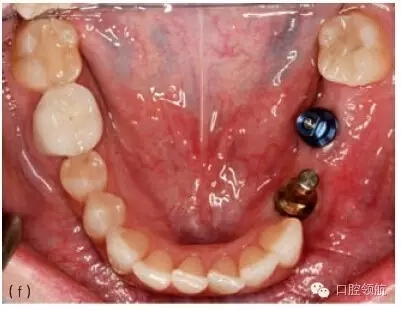

圖10.1 (a)個性化基臺連接在種植體上的牙合面觀。螺絲的長軸對應(yīng)的是種植體的長軸,螺絲的長軸傾斜,基臺螺絲孔通頰側(cè)面。(b)成品基臺的頰面觀,螺絲的入口清晰可見。(c)上頜種植體的轉(zhuǎn)移替代體,反映種植體頰側(cè)傾斜的角度。(d)使用個性化鑄造基臺能獲得良好的美學(xué)效果。(e)轉(zhuǎn)移替代體顯示種植體的方向不平衡。(f)轉(zhuǎn)移替代體在口內(nèi)頜面觀,如圖可見遠(yuǎn)中種植體舌傾。(g)制作診斷蠟型以確定最終修復(fù)體的外形。(h)個性化基臺的代型,遠(yuǎn)中種植體的螺絲入口位于近中舌側(cè)位。固定局部義齒將會粘結(jié)于個性化基臺上。